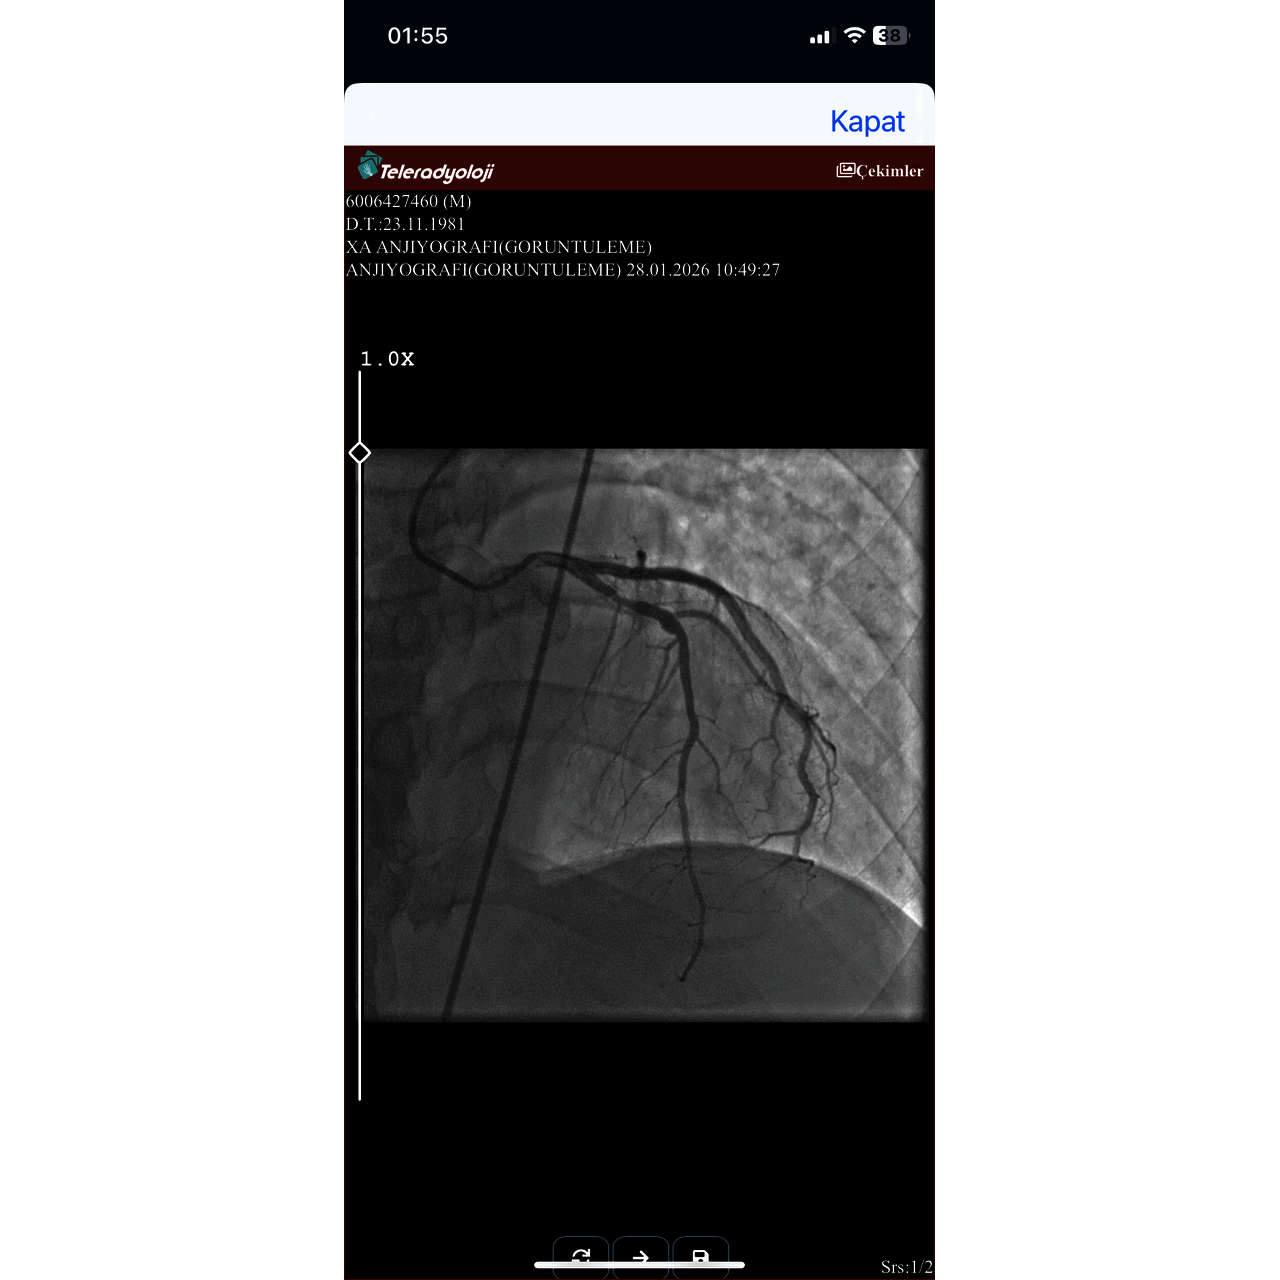

Anjiyo oldum sagolsun yuzde doksan tikali damarimi acti Basarilarin insanlara faydali olmasi dilegiyle iyi calismalar diliyorum